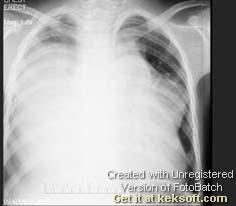

问题 男,13岁,胸痛胸闷2个月,胸部检查如图,最可能的诊断为 ( )

选项 A.心力衰竭并右侧胸腔积液 B.纵隔占位 C.先天性心脏病,房缺 D.先天性心脏病,动脉导管未闭 E.右侧胸腔大量积液

答案 B